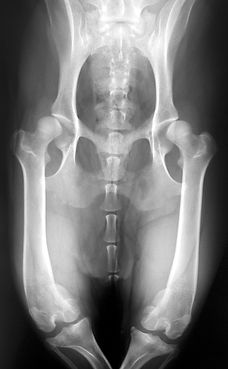

A dog with severe patellar luxation and concurrent limb deformities.